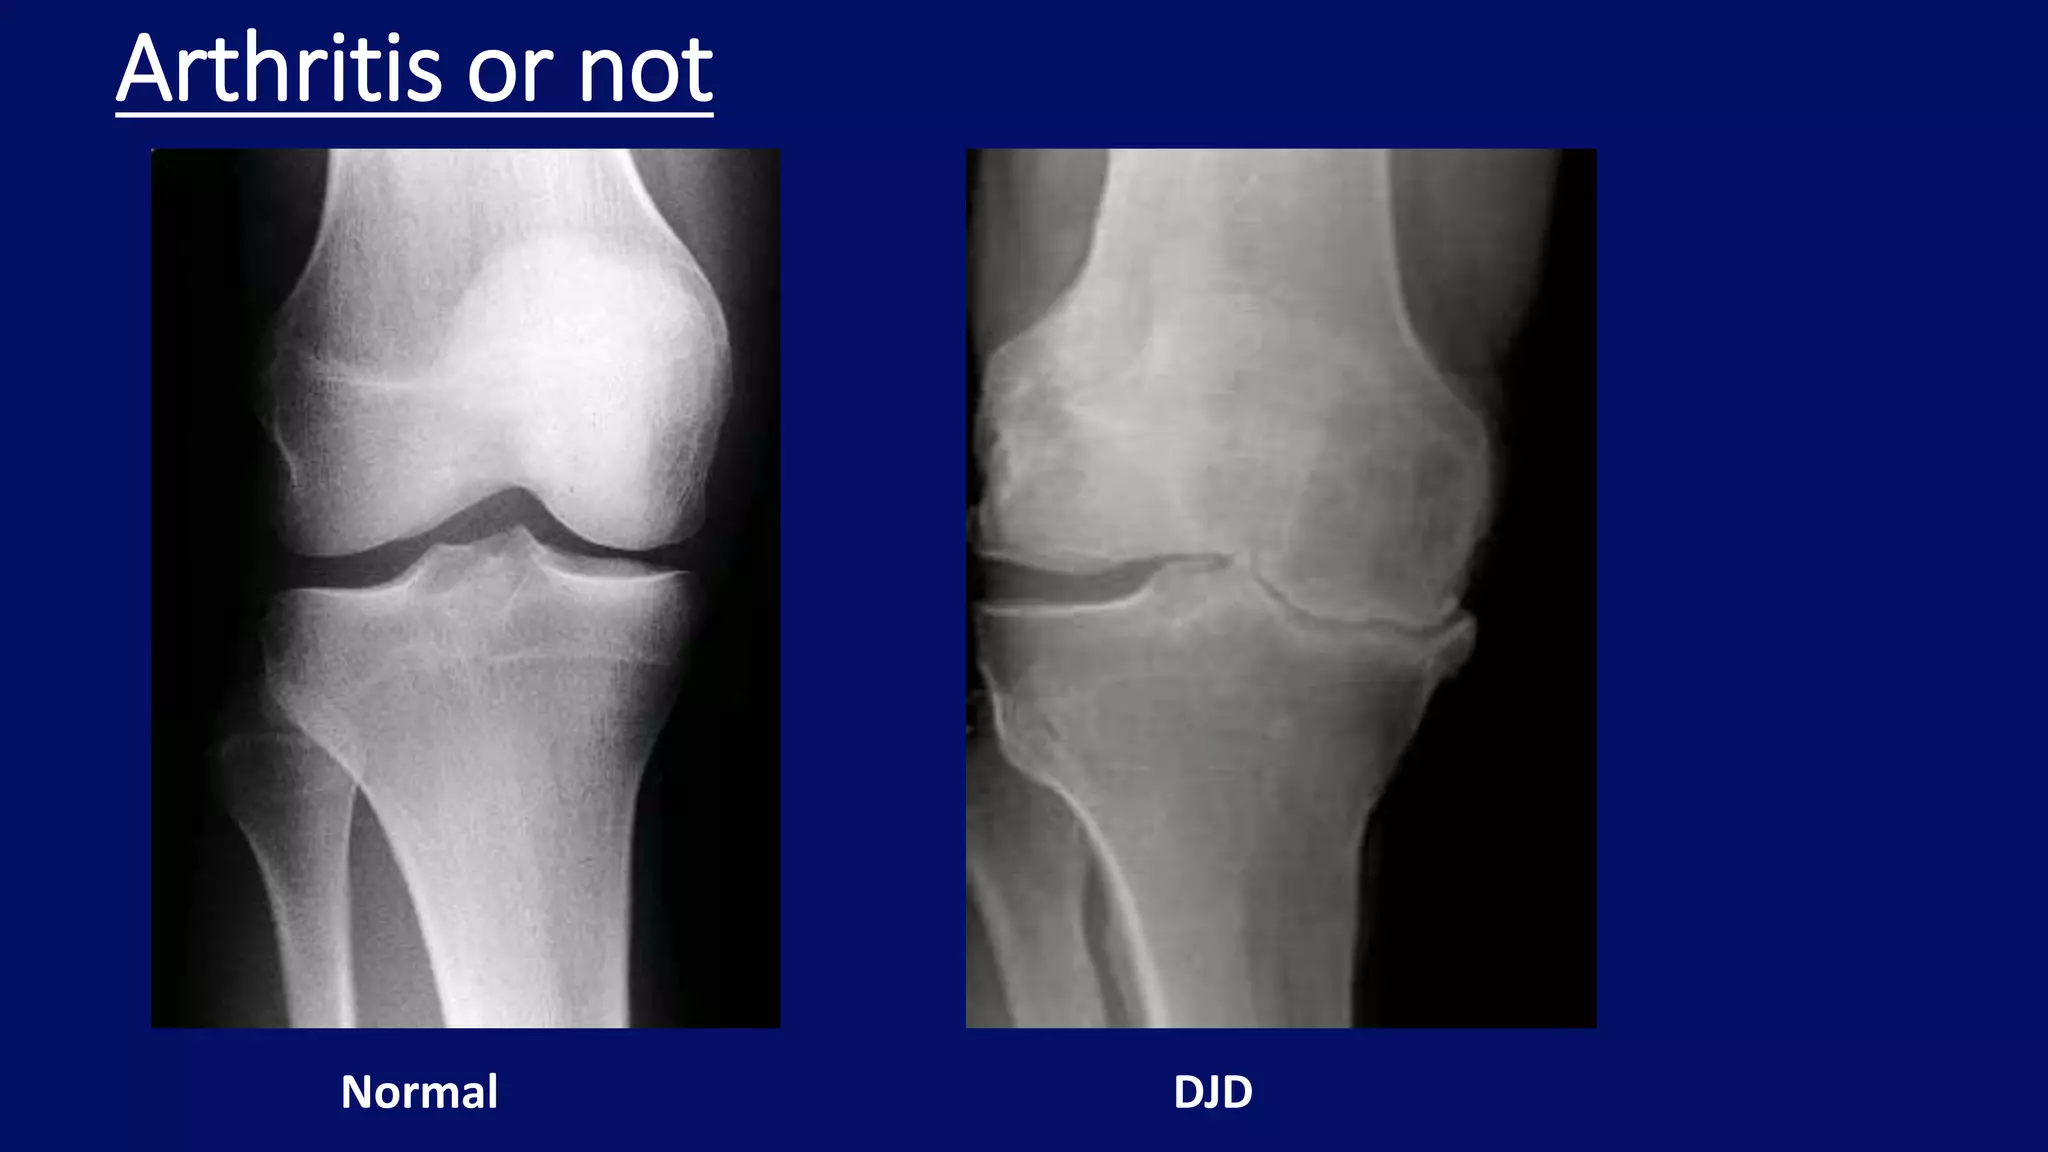

Arthritis or not

Normal DJD